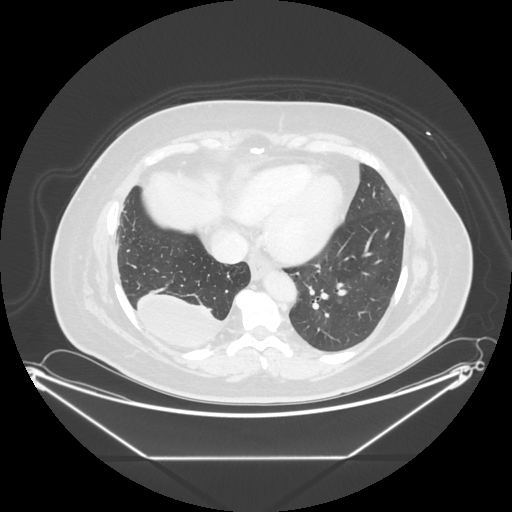

Original NATIVE CT scan (input)

No window - Raw intensity values

Lung window (WL -600, WW 1500 β†’ Low βˆ’1350, High +150)

Mediastinum window (WL 40, WW 400 β†’ Low βˆ’160, High +240)